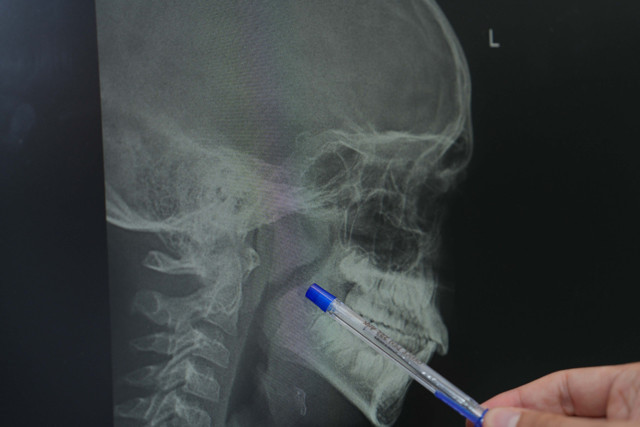

Abone olÇocuğunuzun geceleri huzursuz mu uyuyor? Yatağında sürekli dönüyor, ağzı açık bir şekilde nefes alıyor ve horluyor mu? Gündüzleri ise yorgun ve halsiz mi görünüyor? Bu durum, yalnızca bir gece uykusuzluğundan ibaret olmayabilir. Sık tekrarlayan bademcik ve geniz eti sorunları, minik bedenlerin büyüme ve gelişimini etkileyebilir. Medipol Acıbadem Bölge Hastanesi’nden Kulak Burun Boğaz Uzmanı Op. Dr. İsmail Çelik, ebeveynlerin aklındaki bu sorulara ışık tutuyor. Dr. Çelik'e göre, eğer çocuğunuzun bademcikleri ve geniz eti solunum yolunu daraltarak uykuda nefes durmasına (apne), horlamaya veya sürekli ağız açık uyumaya neden oluyorsa, dikkat edilmesi gereklidir. Benzer şekilde, yıl içinde sık sık tekrarlayan ve antibiyotik tedavisi gerektiren bademcik enfeksiyonları da cerrahi bir müdahaleyi düşündürebilir.

Çocuklarda büyümüş bademcik ve geniz etinin sadece fiziksel değil, gelişimsel riskler de taşıdığını söyleyen Çelik, “Tedavi edilmediğinde büyüme ve gelişme geriliği, yüz yapısında bozulma, sık orta kulak enfeksiyonu ve okul başarısında düşüş gibi sonuçlarla karşılaşabiliyoruz” uyarısında bulundu. Her bademcik sorununun bademciğin tamamen alınmasıyla sonuçlanmayacağını dile getiren Dr. Çelik, “Eğer hastamız sık bademcik enfeksiyonu geçirmiyorsa ve sadece hava yolu tıkanıklığı varsa bademcik küçültme işlemiyle sorun çözülebilir” dedi.